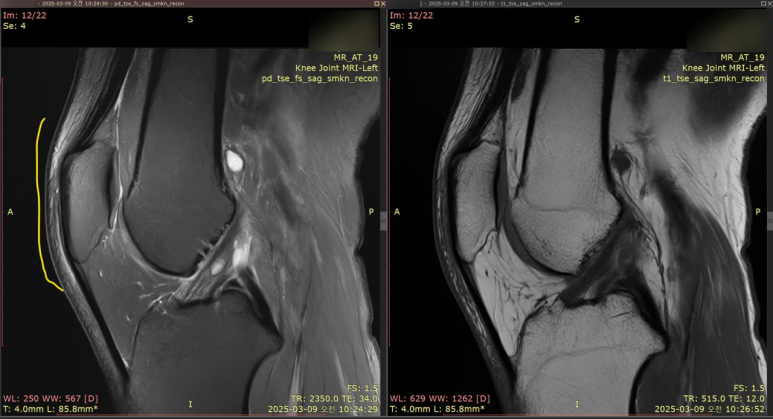

하지만 가져오신 MRI 영상과

환자분의 무릎을꼼꼼히 살펴본 결과

진짜 범인은 따로 있었습니다.

MRI 상 반월판 손상은 보였지만

선명하고 밝은 급성 파열선이 아닌

오랜 시간 달리며 닳아진

'퇴행성 변화' 였던거죠.

놀랍게도 이런 퇴행성 손상은

통증이 전혀 없는 경우도 많습니다

진짜 통증을 일으킨 원인은

무릎뼈(슬개골) 바로 앞에 숨어있던

'슬개전 점액낭염' 이었습니다.